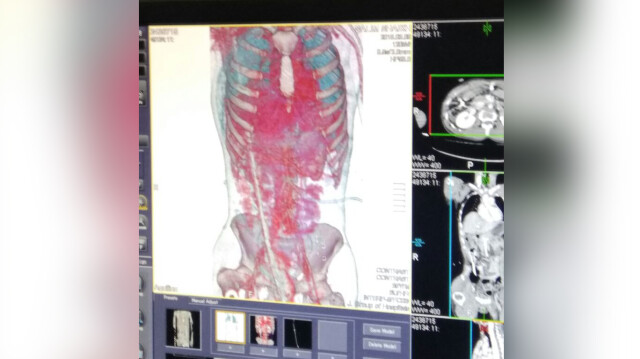

दरअसल 8 मार्च को काम करते हुए सलीम बिल्डिंग की पहली मंजिल से गिर गए थे। नीचे गिरने के बाद सलीम के पेट में एक लोहे का रॉड (सरिया) घुस गया था, यह सरिया बहुत से बुरी तरह से पेट में घुस कर कंधे के बगल से निकल कर आरपार हो गया था। सरिये की लम्बाई 4 फुट थी और यह 8 मिलीमीटर मोटा था। सरिये में फंसे सलीम को सरिया काटकर किसी तरह से निकाला गया लेकिन पेट में घुसे सरिये को कैसे बाहर निकाला जाये एक काफी चुनौतीपूर्ण था। उन्हें आनन-फानन में नासिक के अस्पताल ले जाया गया लेकिन वहां के डॉक्टरों ने हाथ खड़ा कर दिया। उन्हें वहां से जेजे अस्पताल रेफर कर दिया गया।

20 घंटे तक था सरिया शरीर में

अगले दिन 9 तारीख को दोपहर 2 बजे सलीम जे.जे अस्पताल पहुंचा। ये सलीम का हौसला ही था कि उसकी सांसें अभी भी चल रही थीं। 20 घंटे के बाद सलीम का ऑपरेशन शुरू किया गया, तब तक सलीम बेहोश हो चुका था। डॉक्टरों की 2 टीमों द्वारा 5 घंटे तक कड़ी मेहनत के बाद किसी तरह से सलीम के शरीर में धंसा सरिया बाहर निकाला। डॉक्टरों ने बताया कि सलीम की आतें,लिवर, फेफड़े और गर्दन में काफी चोटें पहुंची थीं। सलीम को 2 दिन के लिए आईसीयू में रखा गया था।आईसीयू के बाद सलीम को जनरल वॉर्ड में भेज दिया गया जहां अब उसकी हालत स्थिर बताई जाती है।